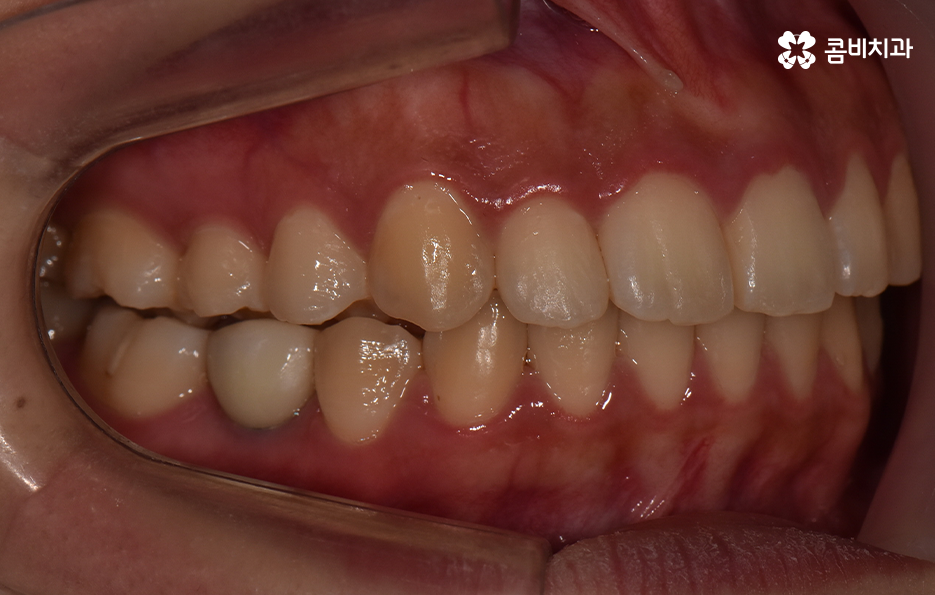

교정을 위해 치과에 가보시면 3D CT 등을 활용하여 3차원 정밀 분석을 통한 치료 후 시뮬레이션 결과까지 직접 보면서 확인할 수 있는데요. 발치 교정을 하면 비발치 교정에 비해서 얼굴 변화가 보다 크기 때문에 치료 후 결과에 대한 예측은 매우 중요한 과정으로 볼 수 있어요

치아교정은 한 번 시작하면 중간에 쉽게 바꿀 수도 없고 어렵게 결심하는 만큼 장기적인 관점에서 치료 계획을 꼼꼼하게 세워야 할 필요가 있는데요. 덧니 발치 교정에 있어서도 단지 치열만이 아니라 치아교정 결과에 있어서 입술 라인과 얼굴형과의 조화까지 생각하고 당연히 교합도 잘 고려하여 발치 여부를 판단한다고 보시면 좋을 거예요

정리하면 덧니 발치 교정의 필요성은 각 개인에 따라 치료 계획은 천차만별이기 때문에 치과에서 정밀 검진과 함께 교정 전문의와의 충분한 상담을 통해서 판단해야 하며 보편적으로는 입술 라인을 고려하거나 돌출 등이 있어서 치열 뿐 아니라 입이 안쪽으로 들어가야 할 필요가 있다면 발치를 하는 것도 좋은 방법이 될 수 있어요